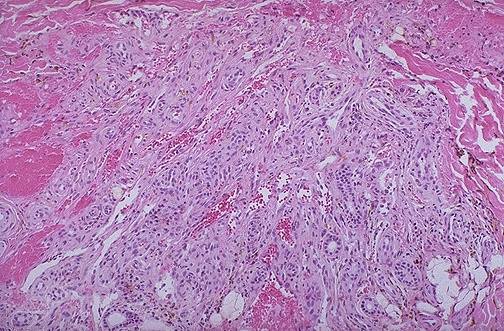

Kaposi's sarcoma microscopically produces slit-like vascular spaces in the dermis of the skin, seen here as a nodule.